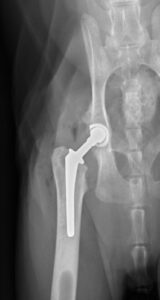

Total Hip Replacement (THR):

THR procedures in dogs and cats are similar to those performed in humans. The procedure involves replacing the femoral head and neck with metal implants, while replacing the acetabulum (the “socket” of the ball and socket joint) with a metal cup containing a plastic inner lining (Figure 4).

As the structure of the hip joint is maintained through the placement of these implants, the hip will function as a normal joint and a normal range of motion should be maintained in addition to normal limb length.

Post-operatively, reevaluation with radiographs will need to be performed with a veterinary surgeon at various time points throughout the life of your pet. This is to ensure that the implants are continuing to function appropriately and to help mitigate potential risks by identifying problems and where necessary, intervening early, which can help avoid catastrophic complications.